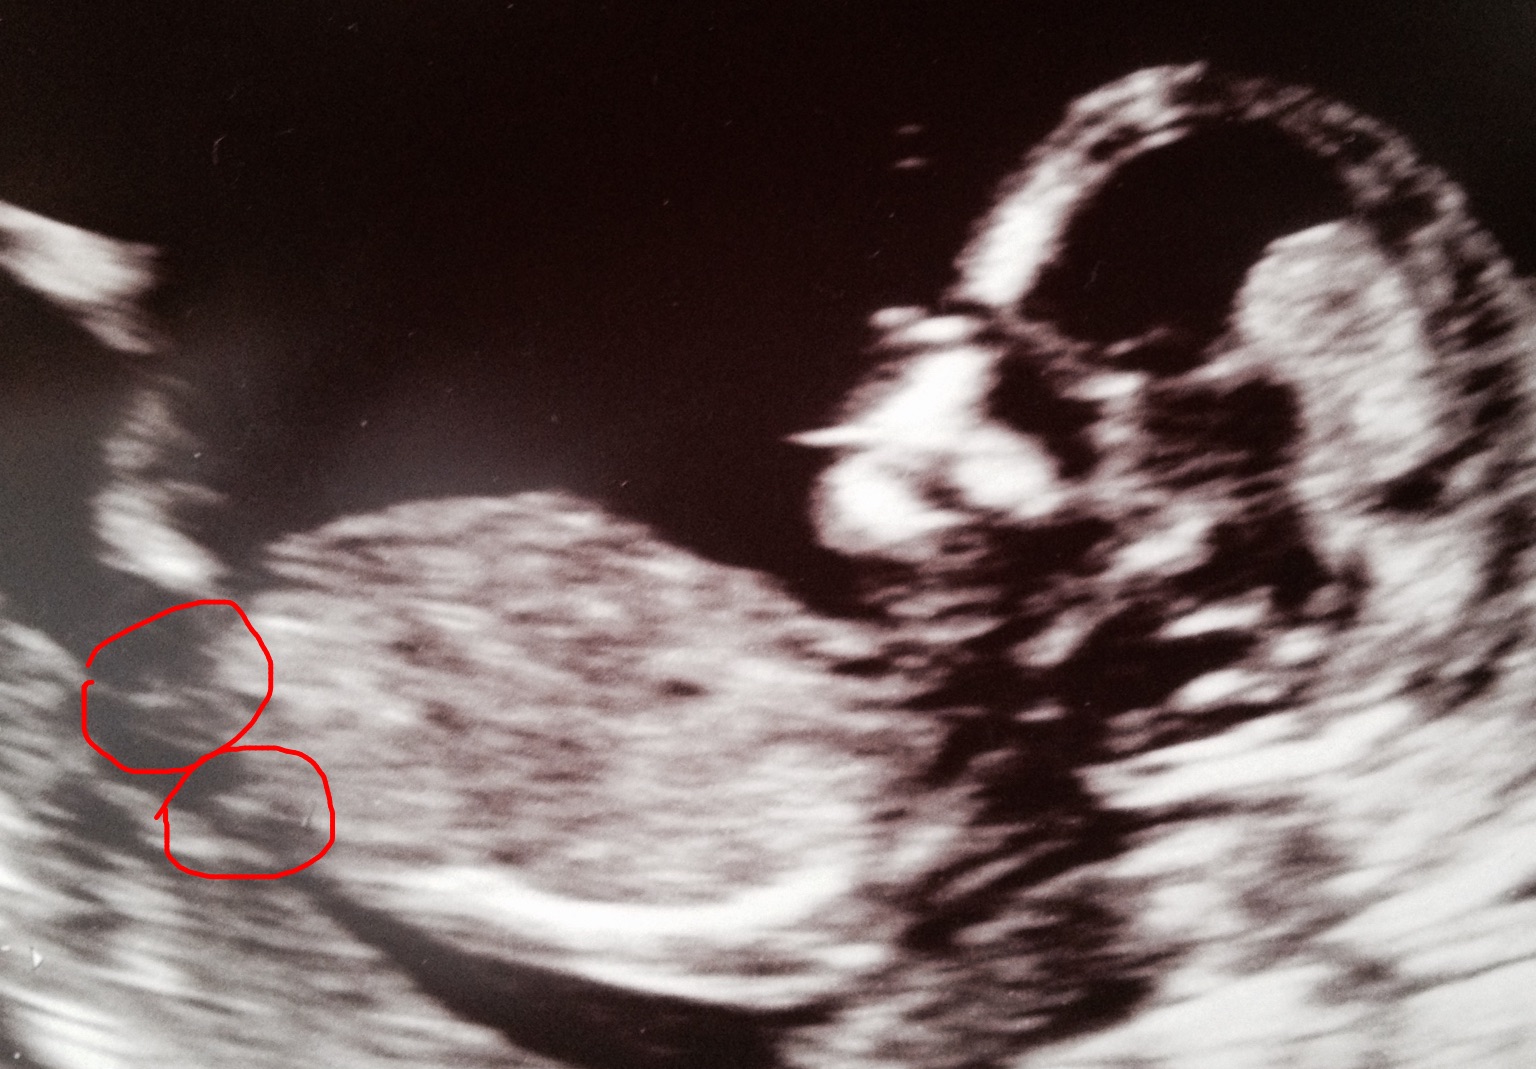

This is my only photo from my NT scan which dated as 12+1.

I was really hoping to be able to guess the gender but I'm not sure if there's even a nub here?

Can you experts take a look? I circled the two areas I thought looked possible - both show forks - would that point to girl?

I'm not sure if there is a nub here. It is not where you circled at least, it would be slightly higher up. More pics?

There is a nub at this stage, although 12+1 is still slightly early, most nubs rise (or not) during the 12th week, so 13-14 weeks is best.

the nub should be higher than where you circled and at that GA it's pretty much 50/50. Congratulations though xx